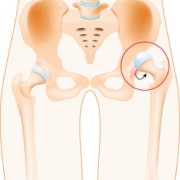

· Telescoping Test – This test looks for possible hip dislocation, where the head of your upper leg bone (femur) moves out of the socket where it normally sits.